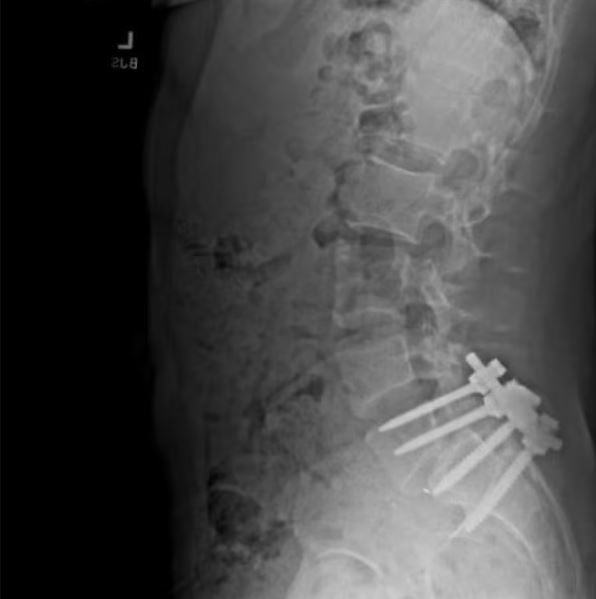

Όπως εξηγεί, ο Μαντζιόνε είχε πάθει παλιότερα μια σοβαρή κατάσταση που ονομάζεται σπονδυλολίσθηση, κατάσταση που χειροτέρεψε έπειτα από μια απόπειρά του να κάνει σερφ κατά τη διάρκεια της παραμονής του στη Χαβάη. «Η σπονδυλική του στήλη δεν ευθυγραμμιζόταν. Μου περιέγραφε την κατάσταση λέγοντας ότι οι κάτω σπόνδυλοι ήταν προεξείχαν κατά μιάμιση ίντσα με αποτέλεσμα να επηρεάζεται σημαντικά ένα νεύρο που τον εμπόδιζε από το να κινείται ελεύθερα», συνεχίζει ο πρώην συγκάτοικος του φερόμενου ως δράστη.

Αρκετές εβδομάδες έπειτα από αυτό, ο Μαντζιόνε φέρεται να υποβλήθηκε σε επέμβαση για να μειώσει τα επίπονα συμπτώματα που είχε η οποία είχε κοστίσει αρκετές δεκάδες χιλιάδες δολάρια, χωρίς όμως να γίνεται αναφορά για το αν είχε ιδιωτική ασφάλιση ή όχι. Μάλιστα, δεν έκανε καμιά αναφορά στη UnitedHealthcare ώστε να μπορεί κανείς να τον συνδέσει με τη δολοφονία του Thompson.

Μάλιστα, ο Μαντζιόνε είχε ποστάρει στον προσωπικό του λογαριασμό και μια ακτινογραφία που είχε βγάλει, στην οποία αποτυπωνόταν πλήρως η σοβαρότητα της κατάστασης.